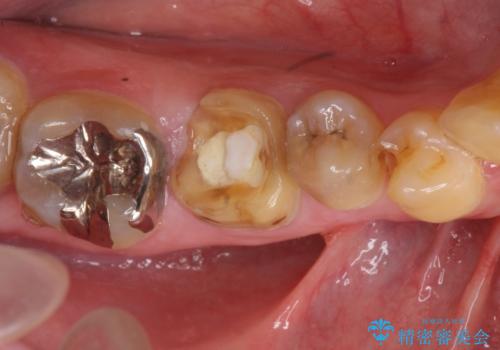

- 奥歯のかぶせものが取れたのと、手前の歯の虫歯治療を希望して来院。

奥歯は神経の治療からやり直し、セラミッククラウンとしました。

手前の歯は1本は虫歯、もう一本もつめものが取れたままでしたので、セラミックインレーとしました。

右下6番は、歯肉縁下カリエスではなかったため、そのまま補綴することが可能でした。